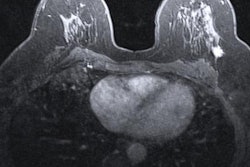

A shortened protocol for breast MRI is just as effective in finding cancer as a full protocol, and it can cut the time a patient is in the magnet by almost 90%, according to a study published online May 11 in Academic Radiology.

"Breast MRI demonstrates impressive cancer detection rates in high-risk women and is known to be the most sensitive screening tool, but is costly and can be difficult to tolerate due to long scan times," Panigrahi and colleagues wrote."Abbreviated MRI protocols may provide opportunity to minimize time, costs, and patient discomfort."

The abbreviated protocol included the localizer series, a precontrast T1-weighted sequence with fat saturation, and one postcontrast T1-weighted sequence with fat saturation, according to the group.